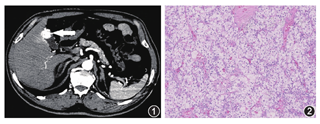

患者,男,71岁。2017年11月体检发现左肾肿瘤,双肾增强CT检查示左肾上极类圆形肿块,大小约6 cm×5 cm,密度不均,增强扫描动脉期呈明显不均匀强化。术前诊断为左肾肿瘤。行腹腔镜根治性左肾切除术。术后病理诊断为左肾透明细胞癌,肿瘤大小约5.7 cm×4.5 cm×3.5 cm,WHO/ISUP核分级3级,肿瘤侵犯肾被膜,紧贴肾周脂肪组织。免疫组化染色检查:Vimentin(+)、CK7(-)、CK8(+++)、CD10(+)、E-Cadherin(+)、P504S(+)、CD117(-)、P63(-)、TFE3(-)、Melanoma(HMB45)(-)、PAX-8(+)、CA9(++)、CD34(-)。病理分期为pT3aN0M0期。术后未进一步治疗,长期门诊随访。2019年11月21日门诊随访,肝胆胰脾彩色多普勒超声检查示胆囊占位。患者无不适主诉,遂转至我院肝胆外科。上腹部增强CT检查(图1):胆囊底部壁增厚,腔内可见凸起软组织密度影,大小约2.0 cm×1.5 cm,增强后有明显强化,考虑胆囊恶性肿瘤。磁共振胰胆管成像检查:胆囊底部可见一结节状等/稍高T1、等T2信号。PET-CT检查未见其他部位转移灶。肿瘤标志物均正常。结合病史及影像学表现,考虑为胆囊恶性肿瘤,肾转移癌不排除。行腹腔镜胆囊切除术,术中快速冰冻病理检查:上皮源性恶性肿瘤,结合病史,首先考虑肾细胞癌转移。术后病理检查(图2):肿瘤大小约2.5 cm×1.6 cm×0.8 cm;胆囊壁内异形细胞浸润性生长,瘤细胞大部分胞质透明,呈实性、巢团状、腺泡状排列,核小,核仁不明显,间质富含纤细的毛细血管网。免疫组化染色检查:Vimentin(+)、PAX-8(+)、CA9(+)、CD10(+)、CK7(-)、CK8(+)、P504S(+)、CK19(-)。结合病史,符合肾透明细胞癌胆囊转移。术后经多学科讨论,予舒尼替尼50 mg,每日1次,4/2方案治疗。随访5个月,未见肿瘤复发和新转移灶。

本病病理检查镜下表现为肿瘤细胞呈实性、巢状、腺泡状排列,胞质丰富、透明,少数淡粉染,细胞边界清晰,核圆形、核仁不明显,间质富含纤细的毛细血管网[5]。免疫组化染色检查Vimentin、CD10、P504S、PAX-8、CA9均(+),CK7(-)支持肾透明细胞癌。研究结果表明,肾源性标志物RCC、PAX-2和PAX-8表达阳性具有鉴别诊断意义[6]。